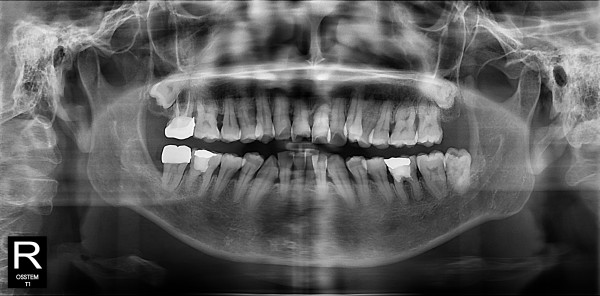

사랑니발치 30대/여성

5e20e086184bc11a2d853605b7813944_1764319778_4025.jpg